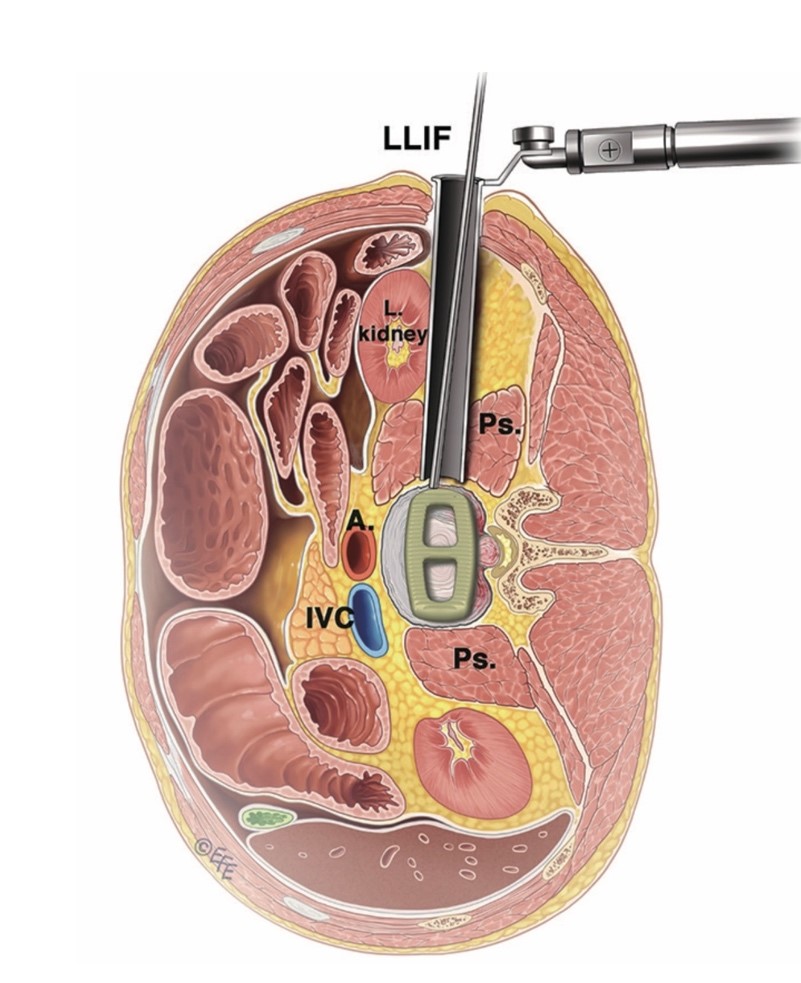

A cirurgia lateral da coluna é uma técnica menos invasiva e pode ser realizada tanto na coluna lombar como na torácica. Nesse tipo de cirurgia, o cirurgião acessa a coluna pela lateral do paciente, tendo como objetivo, assim como a grande maioria das cirurgias de coluna, promover a descompressão de estruturas nervosas e artrodese vertebral com alinhamento da coluna e posterior fusão óssea, mas, por ser menos invasiva, permite uma recuperação mais rápida ao paciente e um retorno às atividades mais breve.

A cirurgia lateral tem a grande vantagem de permitir o acesso à coluna por incisões menores com o menor dano muscular e realizar maior discectomia, que é a retirada do disco doente, o que permite a introdução de implantes maiores, denominados Cages, próteses que servirão como espaçadores entre duas vertebras no lugar do disco doente desgastado; e isso promove uma descompressão das estruturas nervosas e artrodese da coluna com uma recuperação mais precoce do paciente com menos dor no pós-operatório.

A cirurgia lateral é realizada com o paciente em decúbito lateral, ou seja, deitado de lado, comumente o lado esquerdo para cima, é feita uma incisão pequena na pele, cerca de 5cm, o tamanho da incisão vai depender do tipo de paciente e quantos níveis da coluna serão operados.

Através de afastadores especiais sem corte na musculatura é acessada a coluna vertebral e o disco vertebral.

Uso de afastadores especiais com remoção do disco doente e colocação de Cages nos espaços discais.

As siglas XLIF, LLIF, DLIF, OLIF, são abreviações do inglês e significam a cirurgia via lateral da coluna lombar.

XLIF – eXtreme Lateral Interbody Fusion

LLIF– Lateral Lumbar interbody Fusion

DLIF– Direct Lumbar Interbody Fusion

OLIF– Oblique Lumbar Interbody Fusion